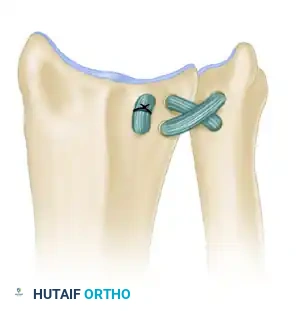

Figure: If primary repair is impossible, the annular ligament can be reconstructed using a strip of fascia lata passed around the radial neck.

- The graft is passed circumferentially around the radial neck and secured to the anterior and posterior margins of the sigmoid notch through drill holes.

- Tensioning must be precise: tight enough to prevent subluxation, but loose enough to permit full, unhindered pronation and supination.

Figure: Completed reconstruction of the annular ligament, restoring proximal radioulnar stability.